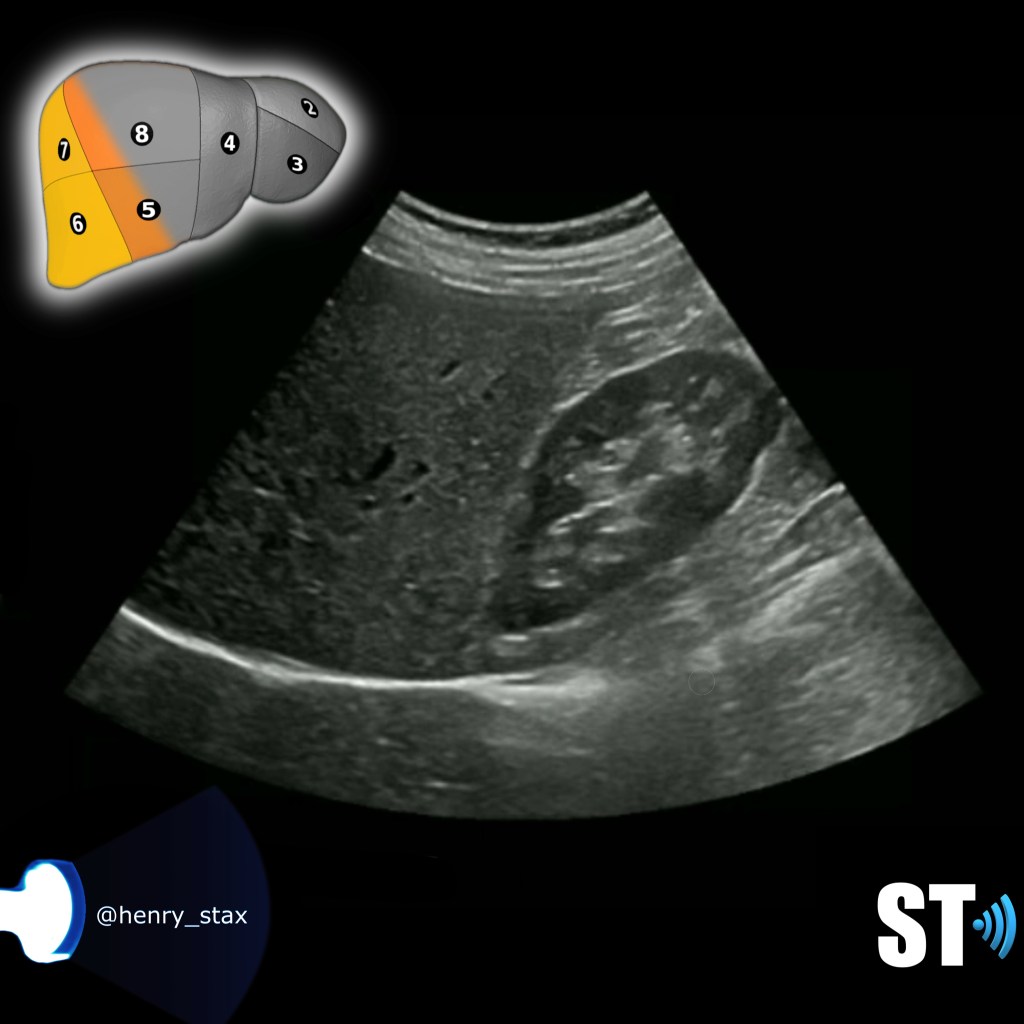

Segments V, VI, VII, VIII

RT Liver lobe and Kidney